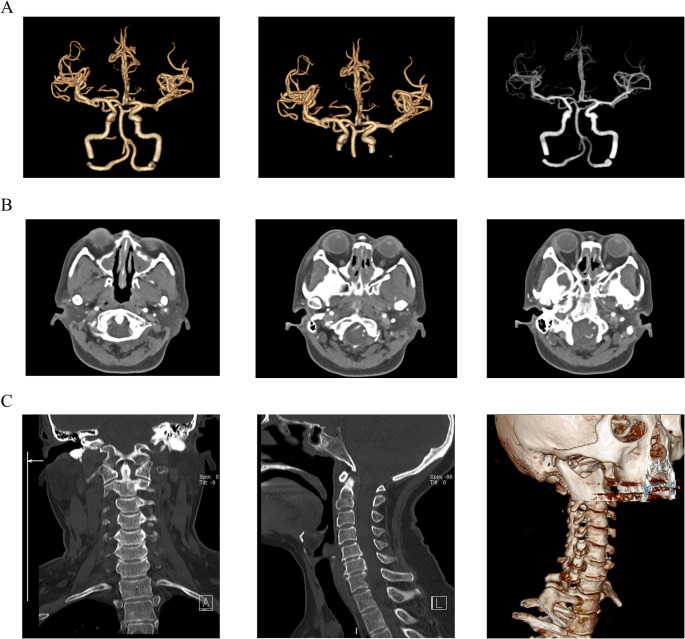

目的:嗜酸性肉芽肿病合并多血管炎(EGPA)是一种罕见的血管炎,其特征是人体组织和外周血中嗜酸性粒细胞增多。在本病例中,我们报告了一位53岁的EGPA女性患者。通过本病例和文献复习,我们希望对EGPA的早期表现、诊断和处理进行阐述,有助于临床医生了解该病,重视dupilumumab诱发EGPA的可能性,提高EGPA的早期诊断率,减少误诊和漏诊。方法:采用美国风湿病学会(American Rheumatology Association, ACR) 2022年制定的EGPA诊断标准;这些标准包括临床表现、实验室检查和病理活检。此外,我们对该病例进行了全面的文献综述。结果:我们报告了一位53岁的女性患者,她在接受dupilumab治疗难治性哮喘和鼻窦炎后出现了严重的周围神经性疼痛。患者的症状、实验室检查结果和鼻咽活检病理结果共同支持EGPA的诊断。当dupilumab转为mepolizumab联合糖皮质激素时,她的周围神经性疼痛和哮喘症状明显缓解。我们的文献综述也提供了Dupilumab和EGPA之间关系的详细讨论。结论:我们报告了一例EGPA合并Dupilumab引起的周围神经性疼痛,mepolizumab对该患者有良好的治疗效果。我们的文献综述显示,虽然dupilumab治疗嗜酸性气道炎症性疾病是有效的,但临床医生必须注意dupilumab诱导或加重egpa的可能性。

Purpose: Eosinophilic Granulomatosis with Polyangiitis (EGPA) is a rare vasculitis characterized by increased eosinophils in human tissues and peripheral blood. In this case, we present a 53-year-old female patient with EGPA. By this case and literature review, we want to explain the early manifestations, diagnosis, and management of EGPA, which will help clinicians to understand the disease and attach importance to the possibility of dupilumab-induced EGPA, to improve the early diagnosis rate of EGPA, and reduce misdiagnosis and missed diagnosis.

Methods: The diagnostic criteria for EGPA established by the American Rheumatology Association (ACR) in 2022 were used; these criteria encompass clinical presentation, laboratory tests, and pathological biopsy. In addition, we conducted a comprehensive literature review on this case.

Result: We present a 53-year-old female patient who developed severe peripheral neuropathic pain after the administration of dupilumab for the treatment of refractory asthma and sinusitis. The patient's symptoms, laboratory examination findings, and nasopharyngeal biopsy pathology results collectively support the diagnosis of EGPA. When dupilumab was converted to mepolizumab combined with glucocorticoid, her peripheral neuropathic pain and asthma symptoms were dramatically relieved. Our literature review also provides a detailed discussion on the relationship between Dupilumab and EGPA.

Conclusion: We present a case of EGPA with peripheral neuropathic pain induced by Dupilumab, and mepolizumab has a good therapeutic effect on this patient. Our literature review shows that although dupilumab is effective in treating eosinophilic airway inflammatory diseases, clinicians must pay attention to the possibility of dupilumab inducing or aggravating EGPAs.